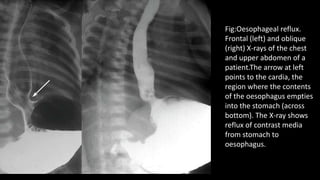

Fig:Oesophageal reflux.

Frontal (left) and oblique

(right) X-rays of the chest

and upper abdomen of a

patient.The arrow at left

points to the cardia, the

region where the contents

of the oesophagus empties

into the stomach (across

bottom). The X-ray shows

reflux of contrast media

from stomach to

oesophagus.